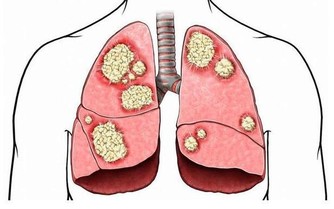

肺部,掌管我們身體中氧氣的輸入和輸出。肺部的健康對我們生命活動都起到著很重要的作用。但是,很多人每天能卻都在做著傷害肺部健康的事情。那就是抽煙。

據研究顯示,抽煙是當今社會導致肺癌的罪魁禍首之一。約40%的慢性阻塞性肺病由吸煙直接引起。吸煙指數(每天吸菸支數×菸齡)大於400者,患肺癌的機率將升高7倍之多。而對於長期吸二手煙的人來說,患肺癌的機率將會提高25%以上。